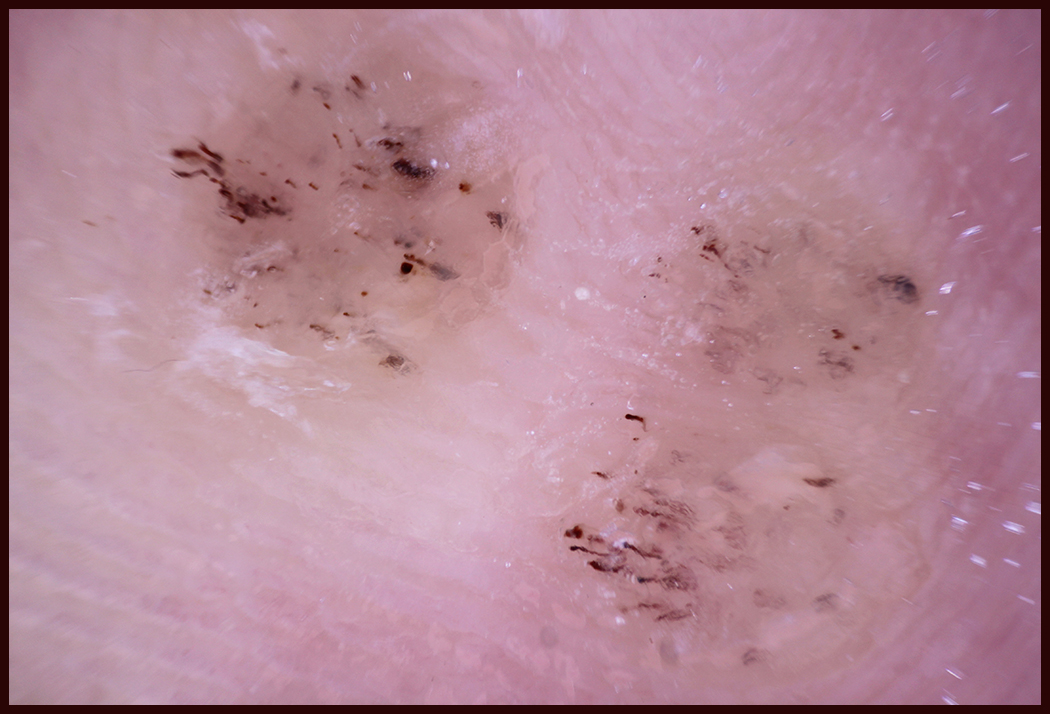

The distinctive dermoscopic features of verrucae plantaris are reddish lines, loops and dots atop multiple, prominent, densely packed, white-haloed dermal papillae. These distinctive dermoscopic features correlate to the hemorrhage within thrombosed capillaries atop the hypertrophied papillae that are visible histologically.4 In addition, plantar verrucae appear as well-defined disruptions of the normal dermatoglyphic pattern with flattening and obliteration of the normal parallel papillary ridges and furrows. One can be assured of complete resolution of plantar verrucae after the parallel ridges and furrows pattern return, and the wart’s prominent dermal papillae, red lines, loops and dots have disappeared.

Plantar pressure keratoses exhibit a translucent or white central core or nucleus without dermal papillae. With intractable plantar keratoses resulting from abnormal pressure and friction, they may present with scattered parallel red and black lines of corneal hemorrhage.5